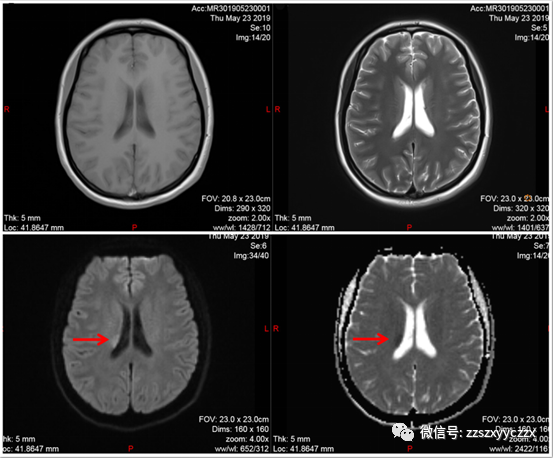

患者于发病后108分钟(2019-5-23 00:48)到达急诊,分诊考虑急性脑卒中,立即进入卒中绿色通道诊疗。00:49立即予以开放静脉通路,同时送检血常规、肝、肾功能、电解质、血糖、心肌酶、凝血功能等检验项目;行头颅CT平扫,结果未见颅内出血(见图1)。01:05急查头颅MRI+MRA+SWI提示右侧颞叶、海马区、侧脑室旁异常信号,考虑急性期脑梗死(见图2)。

A、右侧侧脑室旁异常信号

B、右侧颞叶异常信号

图2 头颅MRI平扫提示右侧颞叶、海马区、侧脑室旁异常信号,考虑急性期脑梗死(A、B中红色箭头所示)